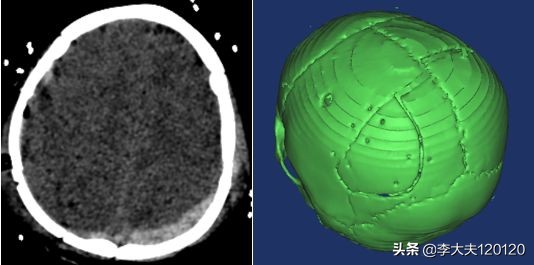

急诊查头颅CT:双侧额顶部硬膜外血肿、顶骨骨折、顶枕部皮下血肿。

见到患儿时,患儿处于昏睡状态,急诊头颅CT显示“硬膜外血肿、顶骨骨折”, 情况非常危急。